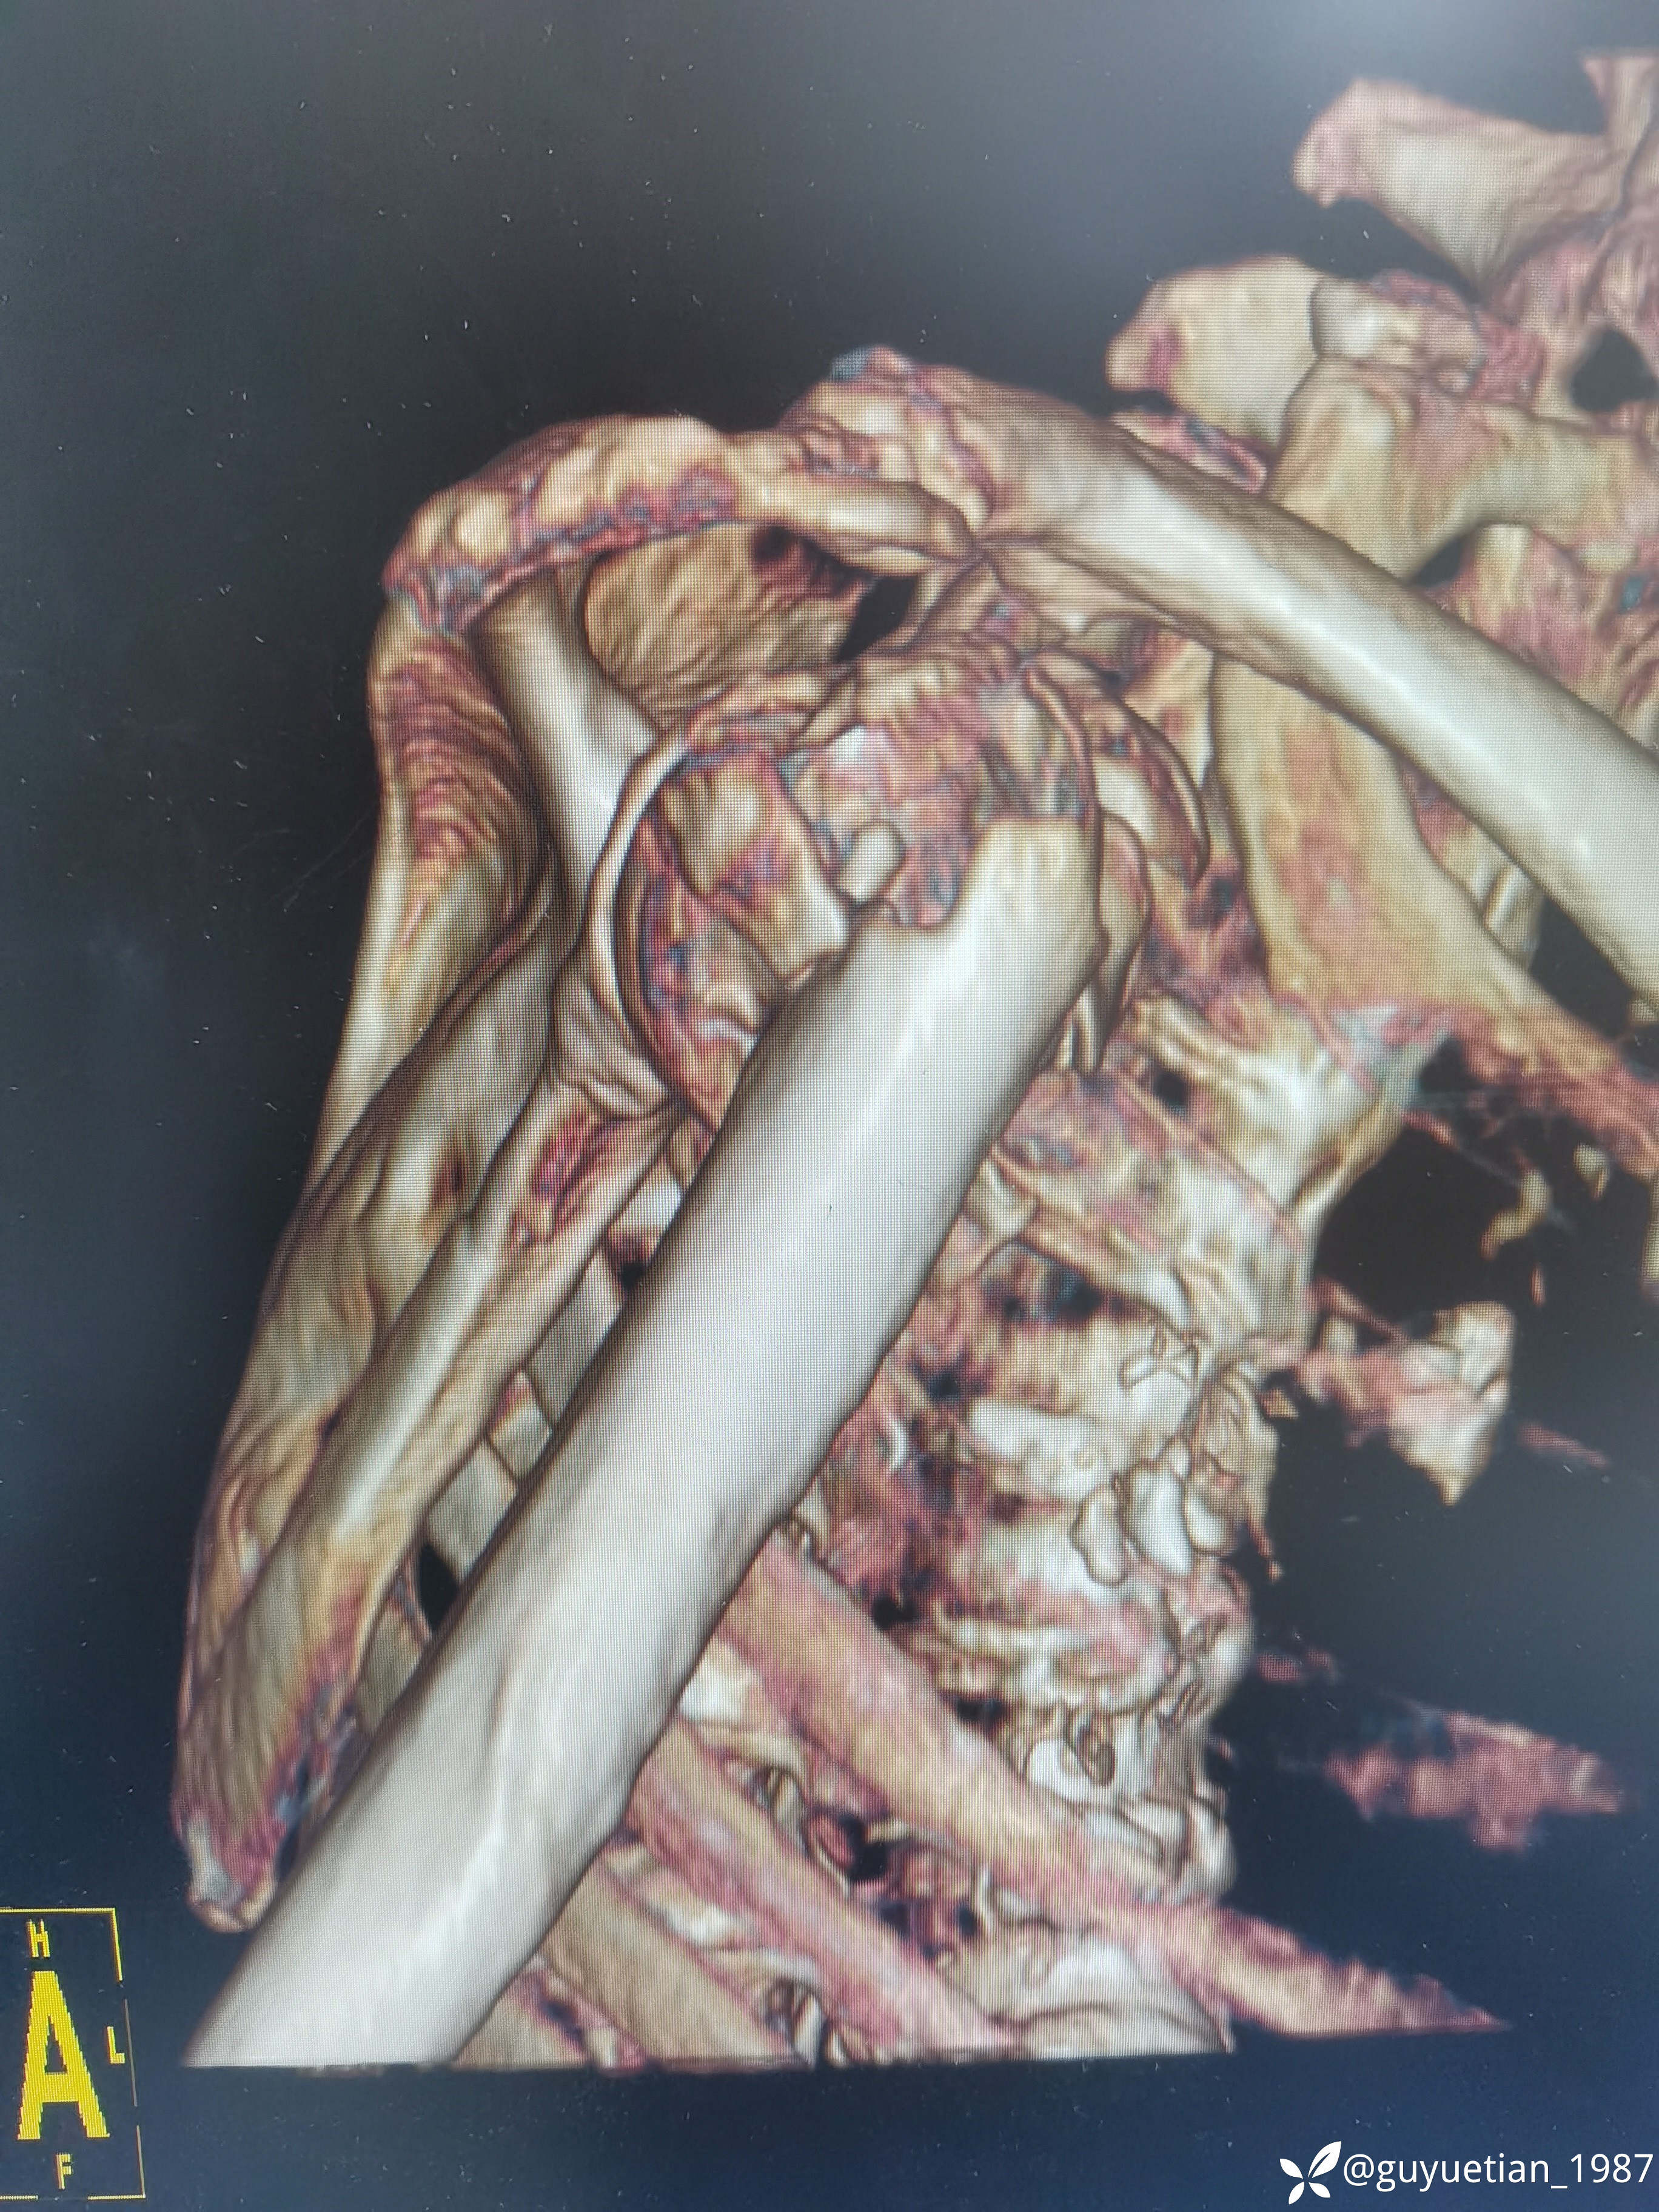

内收型,向前成角

img

家属沟通后倾向于保守,那就尽力而为

可以接受,夹板固定,嘱耸肩、握拳锻炼。